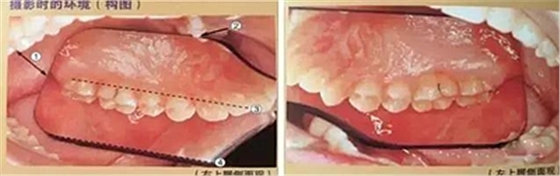

二、全牙列側(cè)面咬合攝影

①口角拉鉤左右手柄中央的位置與咬合平面位于一條直線

②前牙側(cè)口角拉鉤(非攝影側(cè))與前牙不接觸

③磨牙側(cè)口角拉鉤 (攝影側(cè))盡可能打開(kāi)

④患者尖牙位置放置在圖像中央

⑤拍攝比例:1:2-2.4,光圈f22-27, 快門速度1/125, 閃光強(qiáng)度M/4